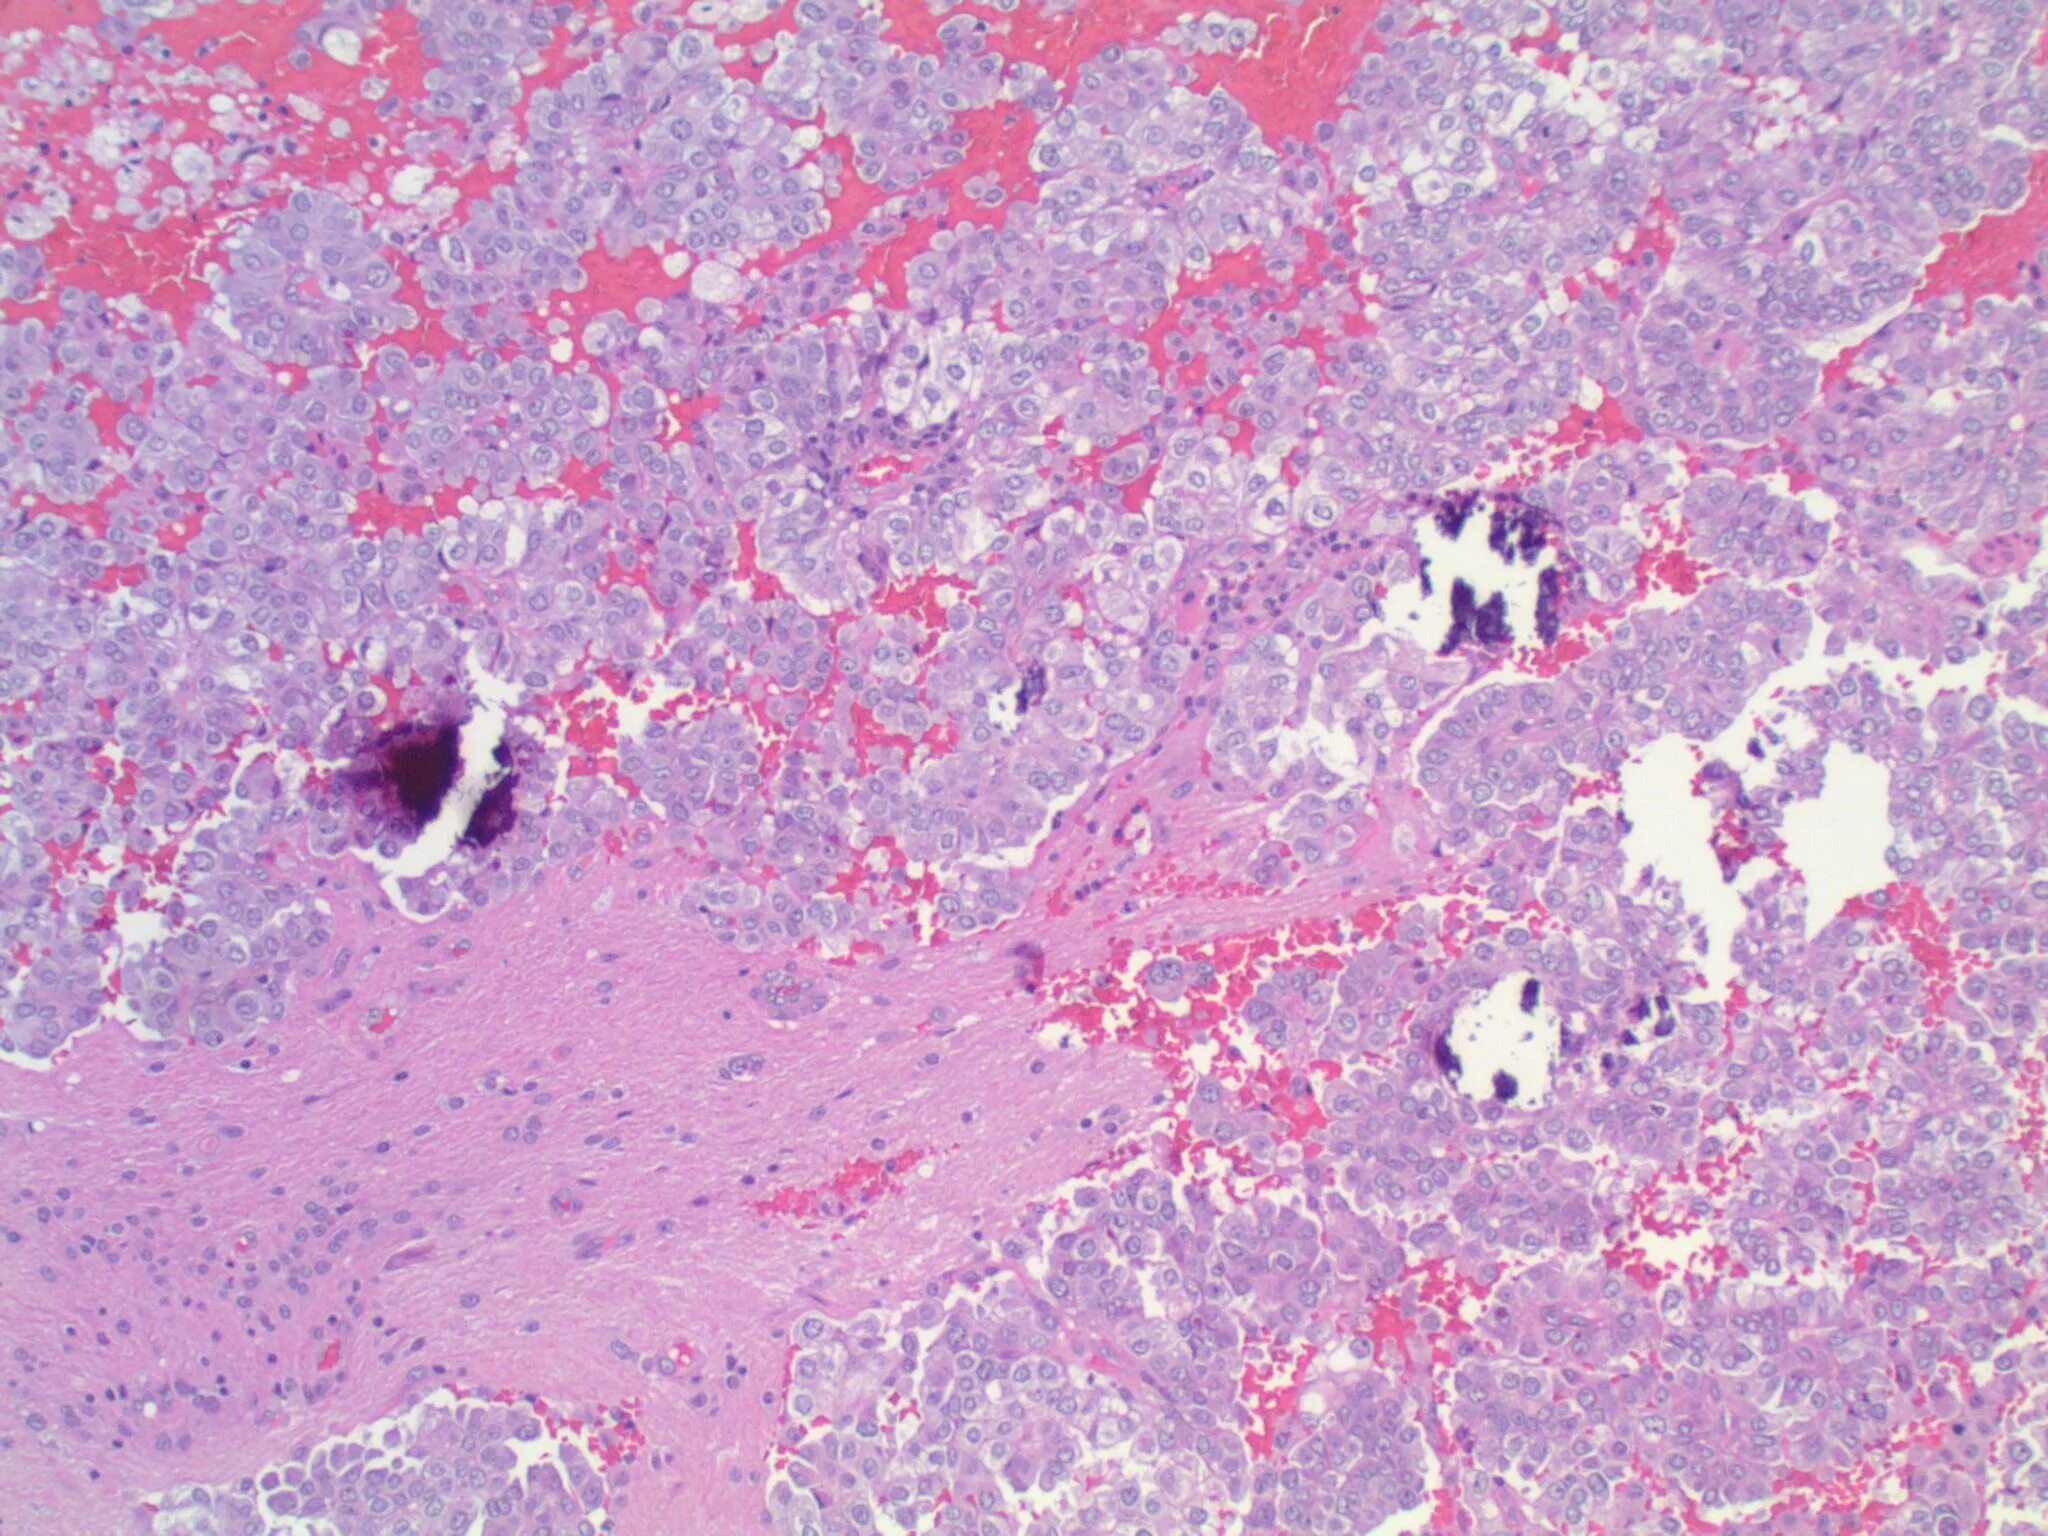

3 метастазы в печени